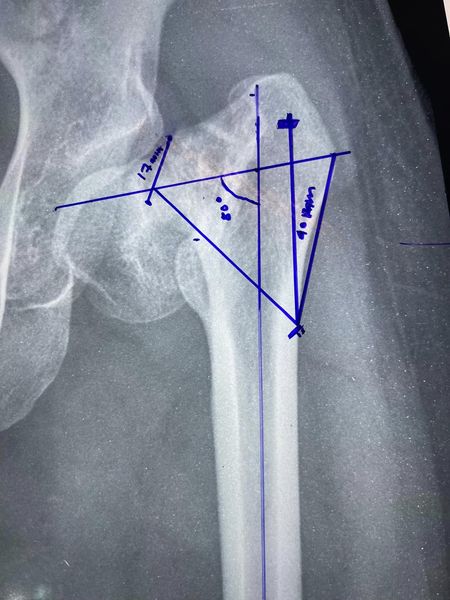

A 19-year-old female with congenital both-side coxa vara (hip deformity) along with scoliosis of the spine and stunted growth, who developed neck of femur fracture of the left side and kept walking with it somehow with support due to sheer negligence of family until now.

Interesting fact: We usually do pre-operative planning and measurements in such cases, the neck length when measured came to 49mm and 50 mm is the shortest screw I could find after calls to all companies who supply such screws in and around Kolkata. Very close call no?